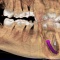

インプラントが入り、噛めるようになるまでの期間を半分以下に短縮できる、抜歯即時インプラント埋入。

抜歯したその日にインプラント埋入し、仮歯まではいる方法です。

CTで事前に十分精査し、ピンポイントで埋入が必要とされる方法です。